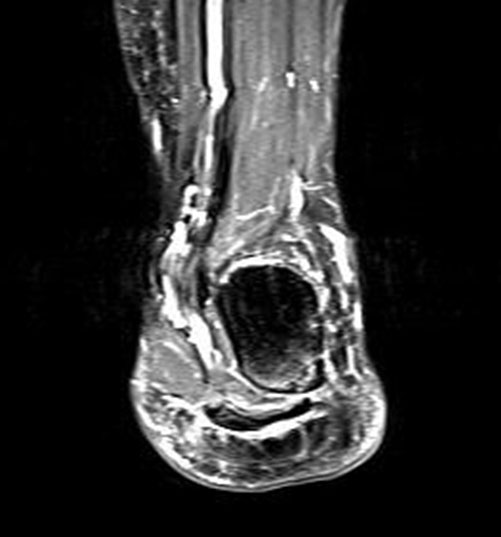

Hier befindet sich ca. 3-5 cm proximal des Tuber calcanei ein als „kritische Zone“ benannter Bezirk, der durch eine ungünstige arterielle Blutzufuhr gekennzeichnet ist (letzte Wiese). Hier finden sich häufig spindelförmige Schwellungen, die bei MRT-Diagnostik nicht selten partielle Nekrosen und Partialrupturen der Achillessehne aufweisen (Abb. 14).

Unabhängig davon können insbesondere chronische Insertionstendinosen der Achillessehne von Partialrupturen (Abb. 15) und erosiven Läsionen des dorsalen Fersenbeines begleitet sein.

Bildgebung

Die sonographische Diagnostik eignet sich primär zur Erkennung schmerzhafter Prozesse im Verlauf der Achillessehne und kann bei Bedarf durch Röntgen bzw. MRT ergänzt werden. Besonders bei längeren Verläufen und kräftigen spindelförmigen Schwellungen (>9mm, Normwert <5mm) im Bereich der kritischen Zone sollte ein MRT zum Ausschluss von Nekrosezonen und Partialrupturen vor Therapiebeginn veranlasst werden. Die sonographisch leicht zu erfassende Veränderung der Sehnendicke im mittleren Sehnenanteil ist ein guter Indikator für die Schwere der Erkrankung und die Beurteilung des Behandlungsverlaufes. Die sichtbaren Veränderungen am distalen knöchernen Ansatz der Sehne sind diskreter.

Insbesondere bei größeren Partialrupturen (Abb. 14) sollten operative Verfahren erörtert werden. Kleinere Partialrupturen sind der ESWT gut zugänglich, wie die beiden nachfolgenden Beispiele zeigen: